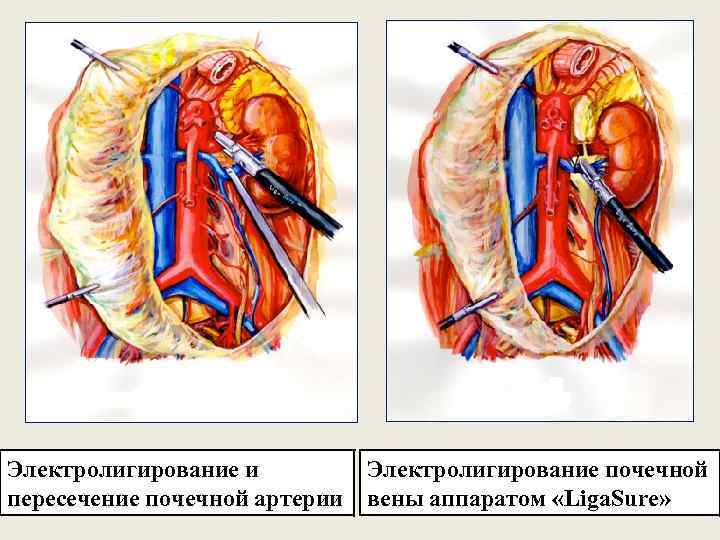

Электролигирование и пересечение почечной артерии Электролигирование почечной вены аппаратом «Liga. Sure»